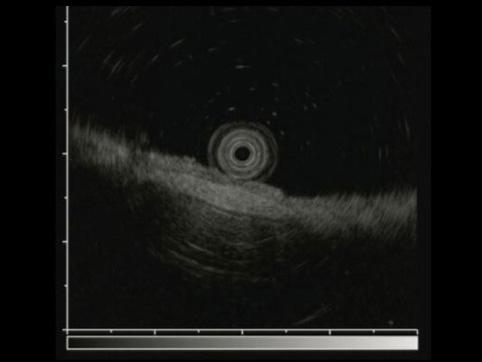

疾病(病理主体)的分类恶性上皮性肿瘤/腺癌

部位(按器官分)胃(部位)/胃角

检查方法超声波

肿瘤的肉眼分类0型(表在型)/IIc型(IIc)

肿瘤最大直径15~19

肿瘤的深度sm